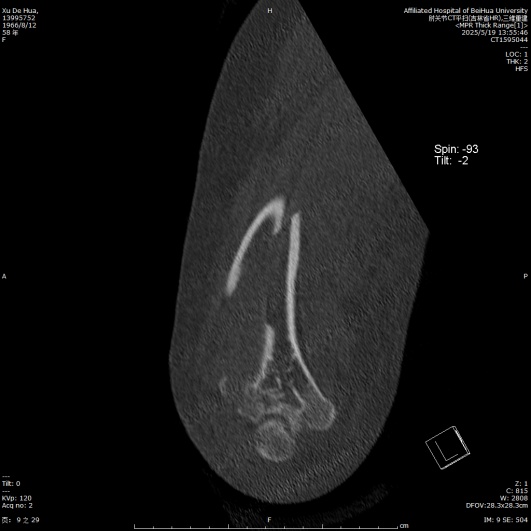

患者徐女士,58岁,因“高处坠落伤致右上臂肿痛、畸形、活动受限2小时”入院。患者于2小时前在家中不慎从3 m高的梯子上不慎掉落摔倒伤及右上臂,即感右上臂剧烈疼痛伴明显活动受限,遂至我院就诊,查体见右上肢三角巾悬吊中,皮肤感觉正常,右上臂中下段及前臂明显肿胀、屈曲畸形,肌张力明显增高,肘关节前侧及内侧皮肤可见张力性水疱,未见明显皮下瘀斑,触痛明显,轴向叩击痛(+),右肩、肘关节活动度因疼痛不能查及,肘后三角关系正常,腕关节及各手指活动度正常,桡动脉搏动可触及,末梢血运良好。急诊行右肱骨X线片检查,提示:右侧肱骨干及肱骨外侧髁可见骨折线影。遂以“右侧肱骨干骨折”收入院。因肱骨干中下1/3段后外侧骨表面有桡神经沟,为防止骨折端不稳损伤刺破神经及肱动脉,故给予右上肢石膏外固定,止痛、消肿等对症治疗,嘱其抬高患肢,抓绕手指。入院后完善右肱骨CT (平扫,三维重建)检查(见图1),提示:右肱骨干、肱骨小头、肱骨滑车、肱骨外侧髁、内侧髁、桡骨头可见骨质多发断裂,断端对位对线欠佳,局部成角,断端分离移位,周围组织增厚,尺骨近段未见异常,右肘关节腔内见片状液体密度影。最终临床诊断为:右侧肱骨干骨折、肱骨滑车骨折、肱骨小头骨折、肱骨内外髁骨折、桡骨头骨折。完善术前相关检查,未见明显异常及相关手术禁忌症,待患肢肿胀情况明显消退后,根据术前影像学资料及患肢的皮肤条件(右肘前侧及内侧皮肤因张力性水疱导致皮肤破溃),最终手术方案选择在插管全麻下行后侧经尺骨鹰嘴截骨入路切开复位双钢板内固定术。

Figure 1. Preoperative CT scan of the elbow joint with plain imaging and 3D reconstruction

1. 术前肘关节CT平扫及三维重建